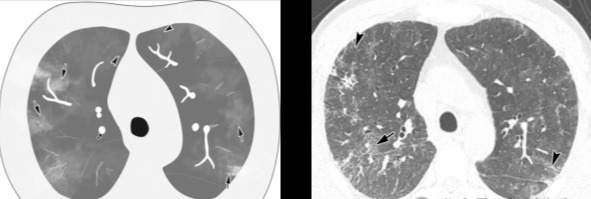

百日咳肺炎CT 表现

支气管血管束增粗且伴 < 2 个肺叶的磨玻璃密度影, 多提示为单纯性百日咳肺炎。(下图:支气管血管束增粗, 两肺下叶基底段少许磨玻璃密度影)

如出现肺内支气管血管束增粗, 伴≥3 个肺叶斑片影、亚段性实变及支气管气象时, 提示患儿病情较重,可能合并其他感染。